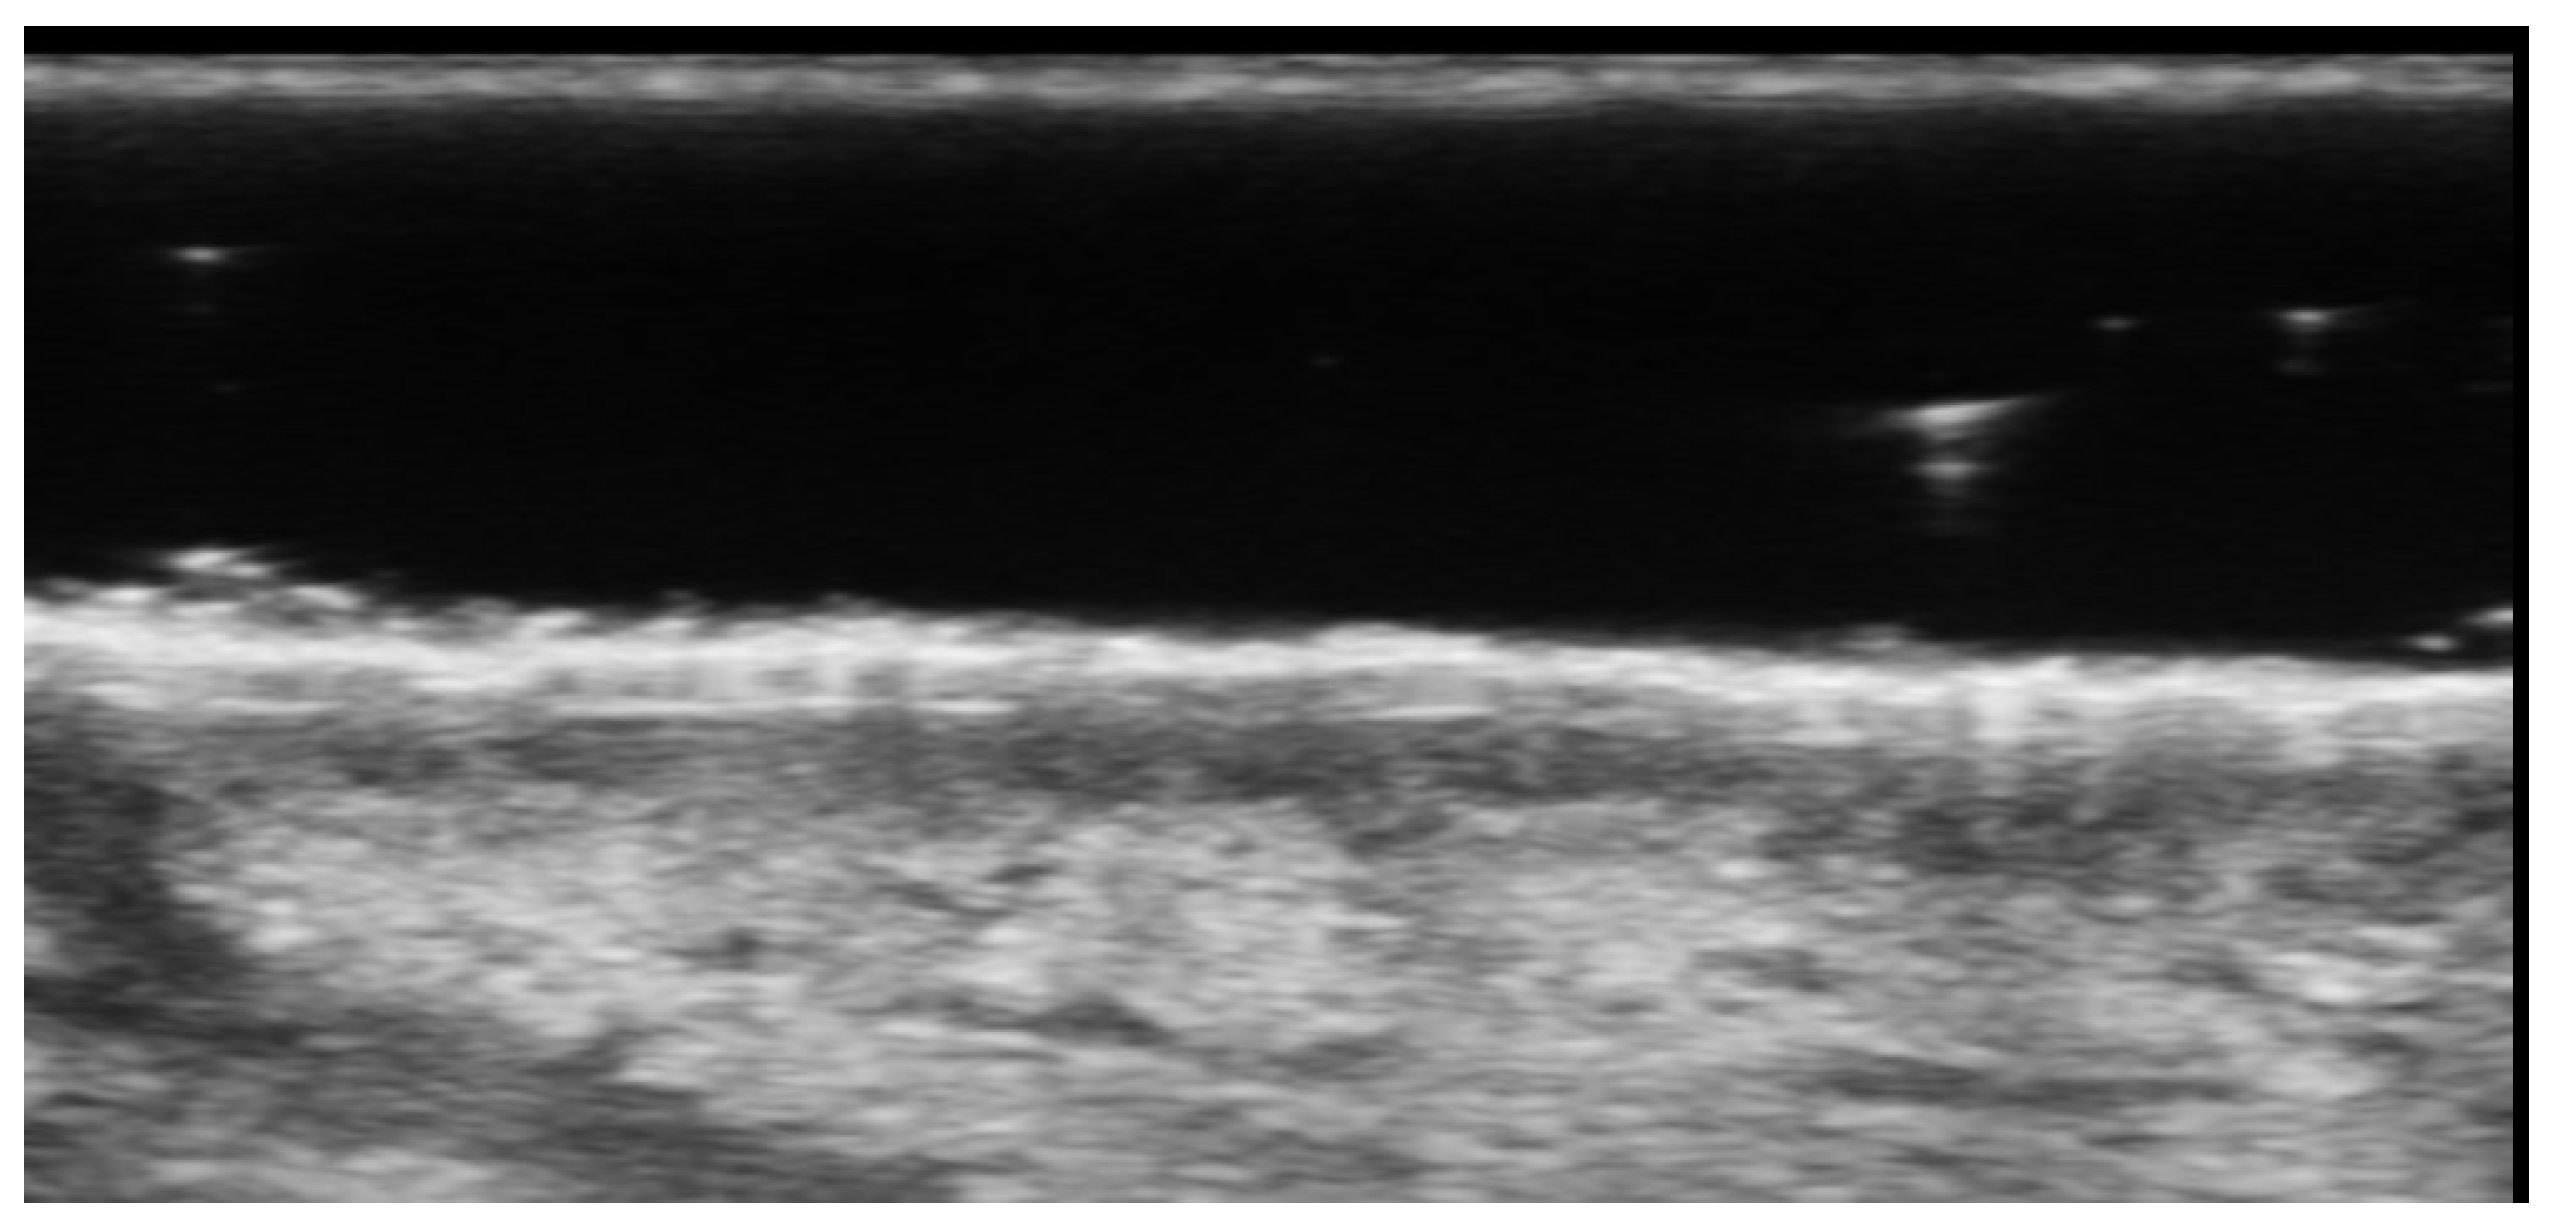

- Svensson, C.; Eriksson, P.; Zachrisson, H.; Sjöwall, C. High-Frequency Ultrasound of Multiple Arterial Areas Reveals Increased Intima Media Thickness, Vessel Wall Appearance, and Atherosclerotic Plaques in Systemic Lupus Erythematosus. Front. Med. 2020, 7, 581336. [Google Scholar] [CrossRef] [PubMed]

- Leonard, D.; Akhter, T.; Nordmark, G.; Rönnblom, L.; Naessen, T. Increased carotid intima thickness and decreased media thickness in premenopausal women with systemic lupus erythematosus: An investigation by non-invasive high-frequency ultrasound. Scand. J. Rheumatol. 2011, 40, 279–282. [Google Scholar] [CrossRef]